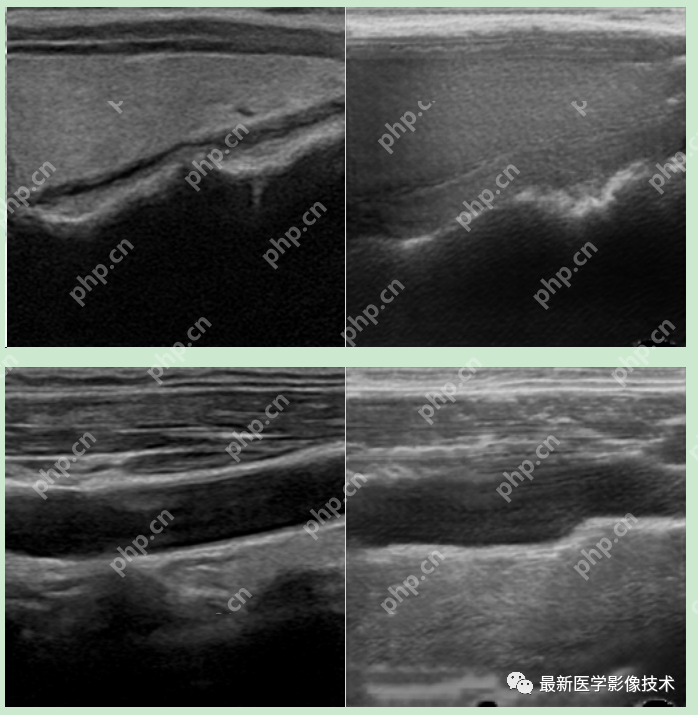

6、测试集部分生成结果

左图为低质量图像,右图为生成的高质量图像。